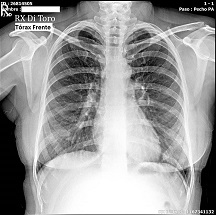

Utilizamos sensores Flat Panel, que nos permiten acortar al Máximo el tiempo de exposición (Dosis de Radiación) y obtener la adquisición inmediata de las imágenes.